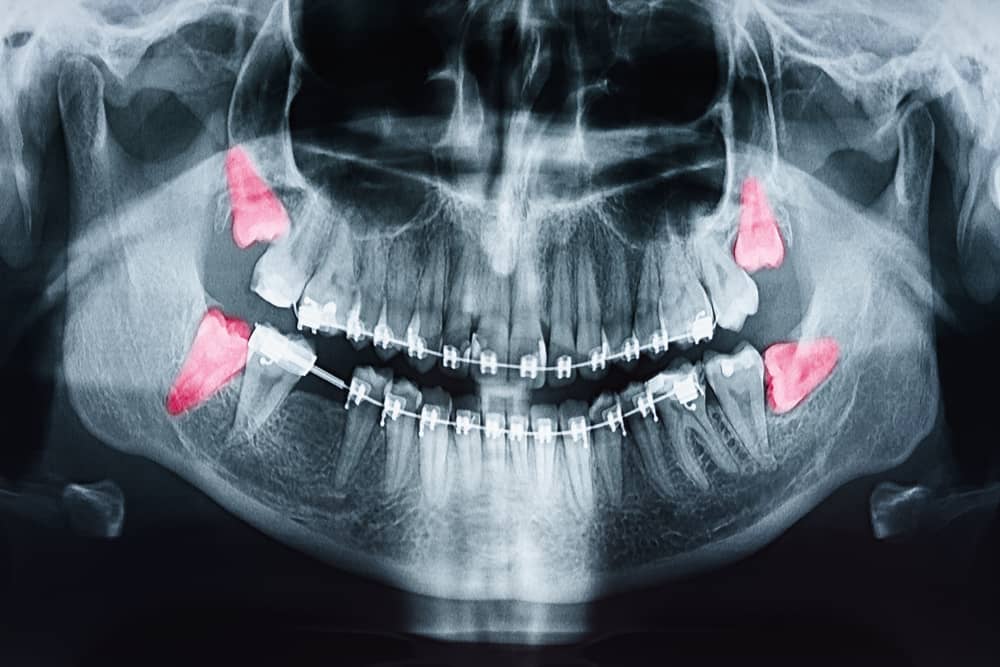

Дентальная галерея: ретинированный зуб клык и его лечение

Раздел: Компас решений